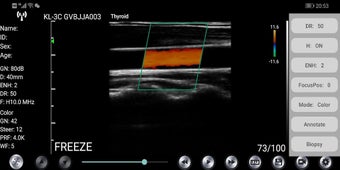

WirelessKUS es una aplicación gratuita de transductor de ultrasonido médico desarrollada por kontedmed para dispositivos Android. Permite al usuario establecer una conexión inalámbrica entre el transductor de ultrasonido y su teléfono inteligente o tableta a través de WiFi. La aplicación ofrece una variedad de funciones como gestión de información del paciente, ajuste de ganancia, control de profundidad, ajuste de frecuencia, ajuste de rango dinámico, control de área de imagen, estado de congelación/en vivo, botón de ajuste de ganancia, herramientas de medición, opciones de guardado de imágenes y videos, selección de canal de WIFI, guía de punción, agregado de comentarios, selección de modelo de imagen, ajuste de posición de enfoque, ENH mejora, THI encendido/apagado y control de rango dinámico.

Para conectar el transductor de ultrasonido con la aplicación, el usuario debe ingresar la contraseña de WiFi por primera vez, que es el número de serie de la sonda en letras minúsculas. Después de la conexión de primera vez, la aplicación se conectará automáticamente con el WiFi de la sonda. La interfaz del software muestra el estado de la sonda y el usuario puede ajustar la configuración utilizando las diversas opciones disponibles. La aplicación también permite al usuario ajustar finamente la ubicación del punto de medición y eliminar todos los resultados de medición con un solo clic.